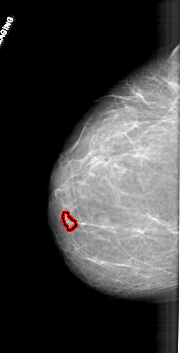

A_1711_1.RIGHT_CC

RIGHT_CC LINES 6166 PIXELS_PER_LINE 3091 BITS_PER_PIXEL 12 RESOLUTION 43.5 NON_OVERLAY

FILE: A_1711_1.LEFT_CC.OVERLAY

TOTAL_ABNORMALITIES 1

ABNORMALITY 1

LESION_TYPE MASS SHAPE LOBULATED MARGINS CIRCUMSCRIBED

ASSESSMENT 4

SUBTLETY 3

PATHOLOGY BENIGN

TOTAL_OUTLINES 1

BOUNDARY